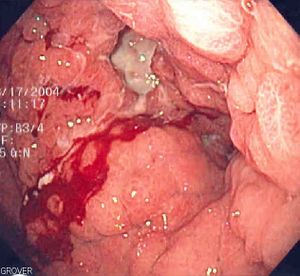

Endoscopic image of linitis plastica, a type of stomach cancer where the entire stomach is invaded, leading to a leather bottle-like appearance with blood coming out of it.